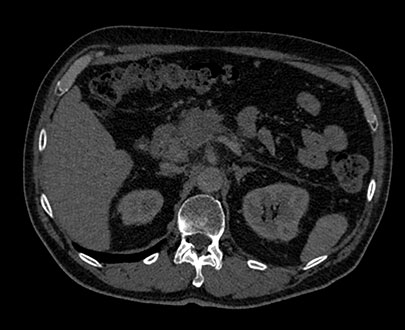

Click the energy level from 40 keV to 200 keV to view structures according to their spectral attenuation properties.

The MonoE view shows synthesized monoenergetic images at predefined keV values from 40 to 200. The appearance of the images changes as the keV values change, even when the window/level settings are unchanged. For example, at lower keV, iodine may appear brighter, and at higher keV, metal artifacts may be reduced.